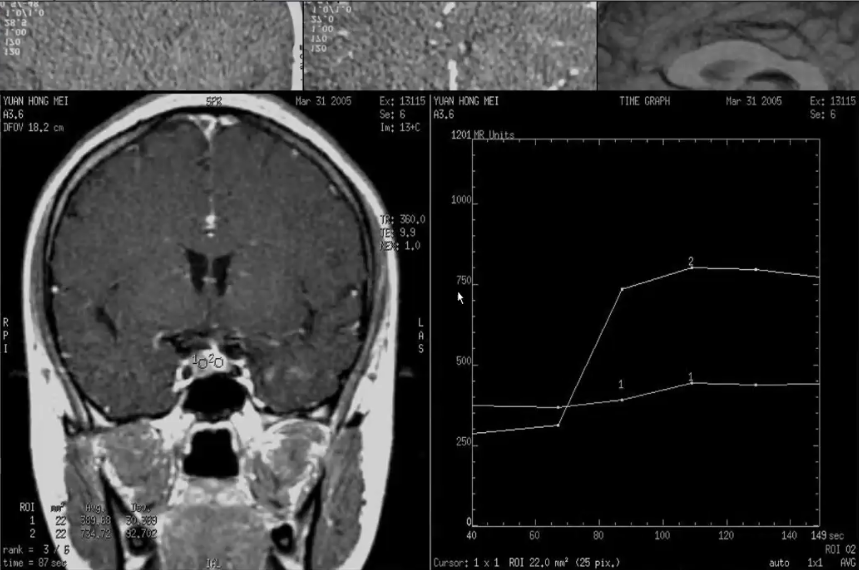

1)平扫:T1WI呈稍低信号,T2WI呈等或高信号

2)动态增强:呈缓慢低于正常垂体组织的强化。为渐进型强化曲线